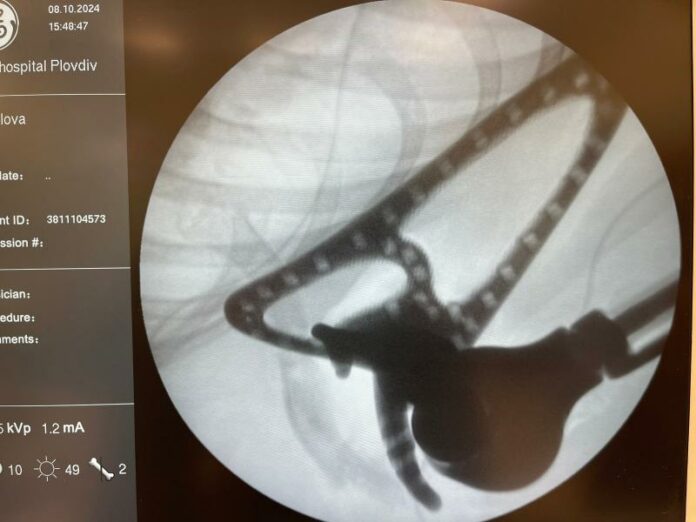

Операцията, продължила 4 часа, беше ръководена от проф. д-р Владимир Ставрев и проф. д-р Любен Стоков. Използваната 3D принтирана ендопротеза е създадена специално за пациентката след предварителен 3D скенер и реконструкция. Протезата, изработена от титан с диамантено покритие и обвита с текстилна тръба, ще позволи на момичето да възстанови движенията на дясната си ръка.